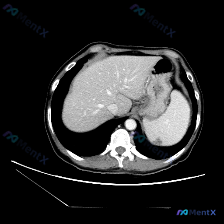

整理了一份关于“脾脏下极局灶性低密度影”的读片思路,感觉这里特别容易踩坑,分享出来和大家一起讨论。 先看影像核心事实 这份是上腹部CT平扫(软组织窗)的单张横断面图像: - 肝脏:轮廓、密度基本正常,未见明确占位 - 脾脏:大小形态正常,但下极靠近背侧边缘处可见一处局灶性低密度影,边界相对清晰,密度...